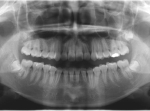

埋伏歯を矯正歯科的に牽引することで、正常咬合を確立できた症例。

埋伏歯は、歯の萌出する隙間の不足、萌出方向の不良、萌出力不足、腫瘍または囊胞などの障害物により萌出路が塞がれている場合などに生じる病気である。いったん萌出が妨げられると、原因が除去されても自然萌出に至らないことが多く、そのままでは埋伏歯が使えないだけでなく、正常咬合が確立できない事態となる。

最良の解決策は、口腔外科的に開窓後、矯正歯科的に牽引し咬合に参加させることである。単に萌出させたと言うだけでなく、牽引後マルチブラケット装置を使用し、正常咬合を確立したケースの提示が求められている。